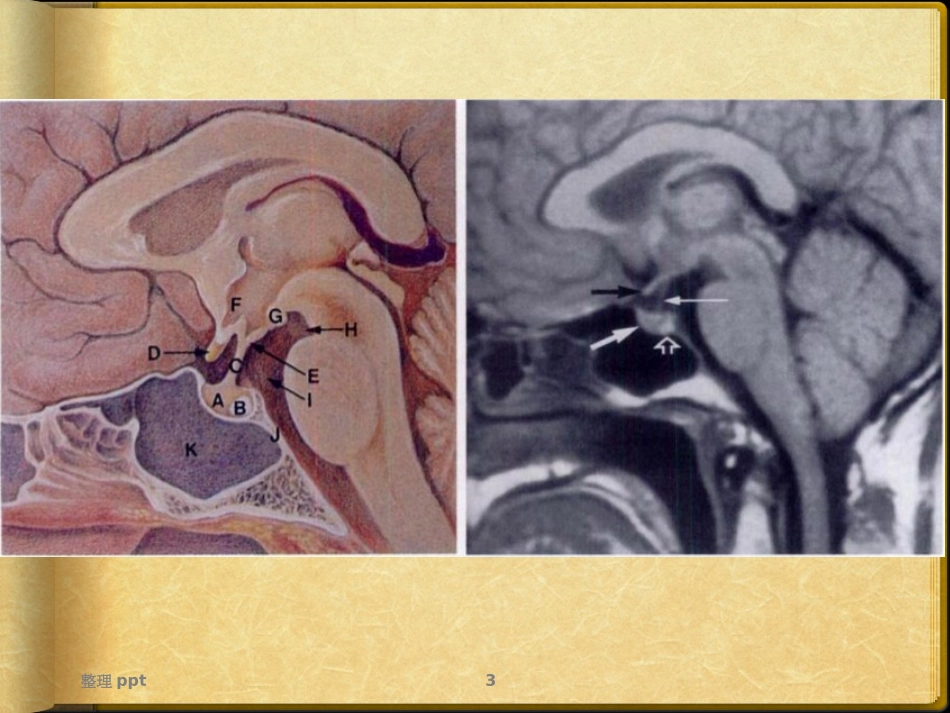

Rathke囊肿整理ppt2鞍区正常解剖整理ppt3整理ppt4整理ppt5整理ppt6整理ppt7整理ppt8整理ppt9Rathke囊肿组织学发生病因Rathke囊肿的发病机理尚存争议,因为Rathke囊的确切胚胎学尚有争议。然而,最常被引用的理论将Rathke囊描述为来源于原口道的背侧中线憩室。整理ppt10胚胎4周时,消化管的颊泡发育成一憩室样结构——Rathke囊袋,继而该囊袋内细胞向颅内生长——颅咽管第3脑室底壁向腹侧外突形成垂体漏斗囊胚胎6周两部分相接触而融合形成垂体原基Rathke囊大约于胚胎7~8周时与原始口腔间通道闭塞,随后Rathke囊袋前壁和后壁增生形成垂体的前叶和中间部,漏斗部增生则形成垂体后叶在垂体中间部残留一小腔隙,该腔隙在大多数成人逐渐被上皮细胞内折所填充,但亦有部分成人可一直保持一般情况下无临床意义,当腔隙内分泌物增加,腔隙明显扩张成为囊肿时,即形成Rathke囊肿整理ppt11流行病学占原发性颅脑肿瘤样病变1%以下发病年龄多在30岁以上,且女性多于男(国内文献)国外文献报道:儿童发病率并不低于成人可发生于任一年龄段发病高峰年龄:40-60女>>男,可达3:1整理ppt12流行病学临床症状:主要是压迫周围组织结构产生占位效应头痛——首发症状垂体功能障碍:男性:性欲降低;性功能减退女性:泌乳;不育视力下降或视野缺损——第二首发症状:病灶压迫视交叉致双颞偏盲整理ppt13MRI表现部位:Rathke囊生成移行通道的任何一点——垂体的中间部或远侧部最多见可完全位于鞍内,亦可为鞍内并向鞍上延伸,完全位于鞍上少见外形大多呈圆形或卵圆形,经鞍隔孔向鞍上延伸,可呈哑铃形,囊壁菲薄,不易观察整理ppt14Rathke囊肿MR信号多种多样若含有黏蛋白成分、胆固醇和脱落碎片则信号多变按照T1WI分为(相较正常脑白质):高信号;低信号;等信号典型者:T1WI低信号,T2WI高信号但是,只有1/3为典型信号,余2/3呈T1WI高-等信号。MR表现整理ppt15MR表现囊液信号特征主要取决于蛋白含量高低蛋白浓度<100000mg/l,T1WI低信号,T2WI高信号蛋白浓度100000~170000mg/l,T1WI高信号,T2WI高信号蛋白浓度>170000mg/l,T1WI高信号,T2WI低信号整理ppt16胆固醇含量影响囊液MR信号吗?整理ppt17Rathke囊肿的MR表现反映其内成分T1WI信号的增加、T2WI信号的降低只与其内含蛋白成分的多少有关,与胆固醇的含量无关整理ppt18增强扫描,囊壁多不强化但是,如囊壁鳞状上皮化生或合并感染时,囊壁增厚并可强化整理ppt19整理ppt20典型病灶信号特点80岁,男性整理ppt21T1WI低信号:生长缓慢,且体积大,经常引起视野偏盲T1WI等或高信号:发现时病灶一般较小整理ppt2243岁,男性整理ppt2325岁,女性整理ppt24整理ppt25囊内结节:贴壁型;漂浮结节(17-78%)囊内结节及囊内不均匀沉积物一般无增强表现偶有例外沉淀物病理上:脱落皮屑与黏蛋白混合物整理ppt2650岁,女性整理ppt2728岁,女性整理ppt28Rathke囊肿卒中罕见钙化少见,曲线状的,沿着囊壁出现的部分钙化整理ppt29Rathke囊肿DWI呈明显高信号,ADC图呈低信号与囊液中分泌物的蛋白质黏稠物质影响水分子扩散有关有助于鉴别诊断整理ppt30鉴别诊断Rathke囊肿——垂体微腺瘤共同点:局限于鞍内,T1WI低信号不同点:边缘更光滑锐利信号更低增强扫描基本无强化如小的囊肿T1WI呈高信号,更提示Rathke囊肿小的垂体腺瘤很少出现卒中整理ppt31鉴别诊断较大的T1WI高信号Rahtke囊肿——垂体瘤卒中共同点:T1WI高信号,位于鞍内及鞍上不同点:垂体卒中——囊壁较厚而欠均匀增强较明显囊内常残留肿瘤组织亦可出现增强Rathke囊肿——内容物无增强(无实性成分)较少出现蝶鞍的扩大并可见正常垂体组织短期随诊囊液信号无变化整理ppt32鉴别诊断Rathke囊肿——囊性或囊实性颅咽管瘤共同点:鞍内向鞍上延伸或完全位于鞍上的二者起源相同不同点:颅咽管瘤多见于儿童,占儿童期鞍区肿瘤的50%40~60岁为第二发病高峰期鞍上多见,完全位于鞍内少见囊液MRI信号为鞍区占位中最为复杂多变且不均匀增强后囊壁和实性部分强化,而囊性部分无强化如Rathke囊肿囊壁上皮鳞状上皮化生或合并感染,囊壁增厚可强化,与颅咽管瘤不易鉴别整理ppt33Thankyou!整理ppt